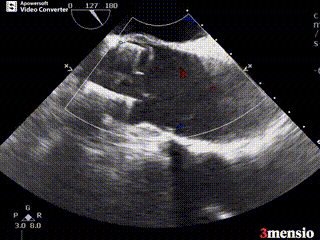

术前超声影像图